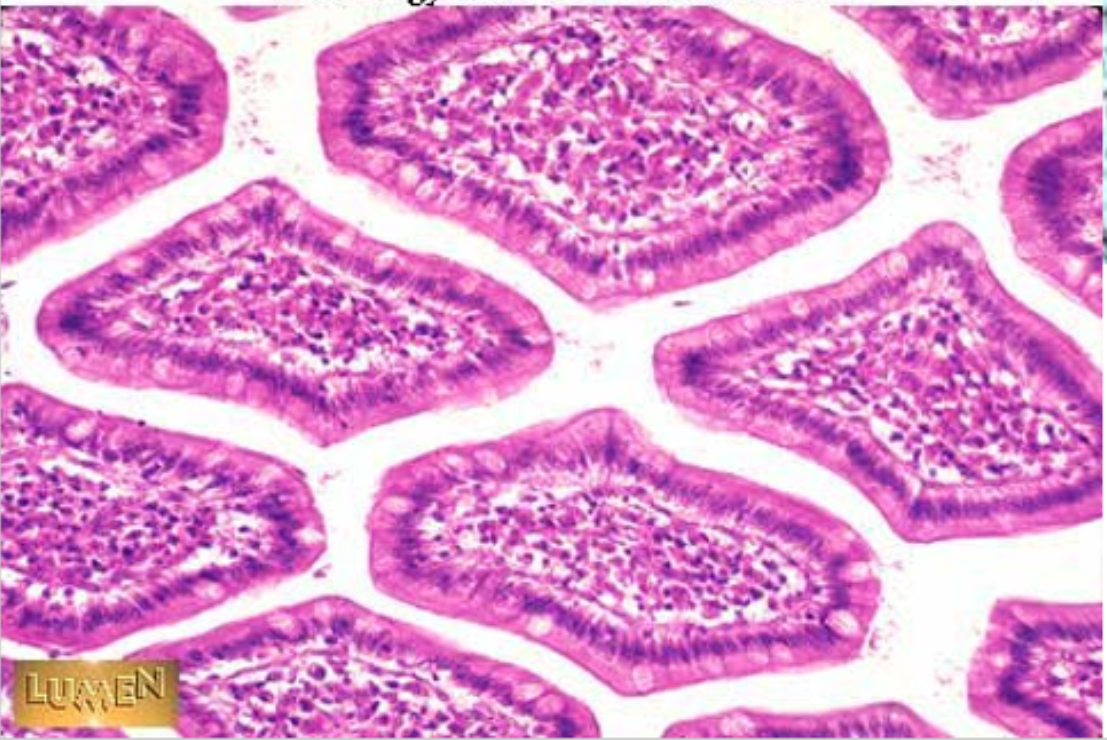

plicae circulares

green

villi

crypts

blue

lamina propria

black

simple columnar epithelium